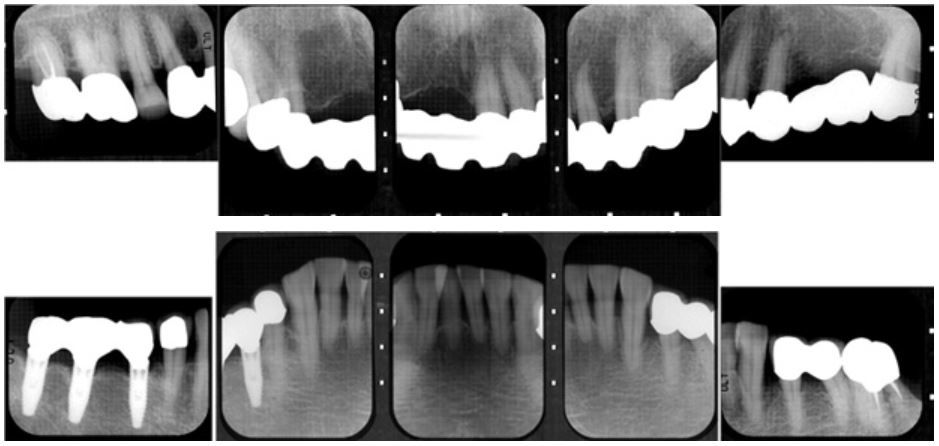

歯周組織再生療法症例(65歳・女性)

初診時

再生療法治療終了2年後

再生療法治療終了5年後